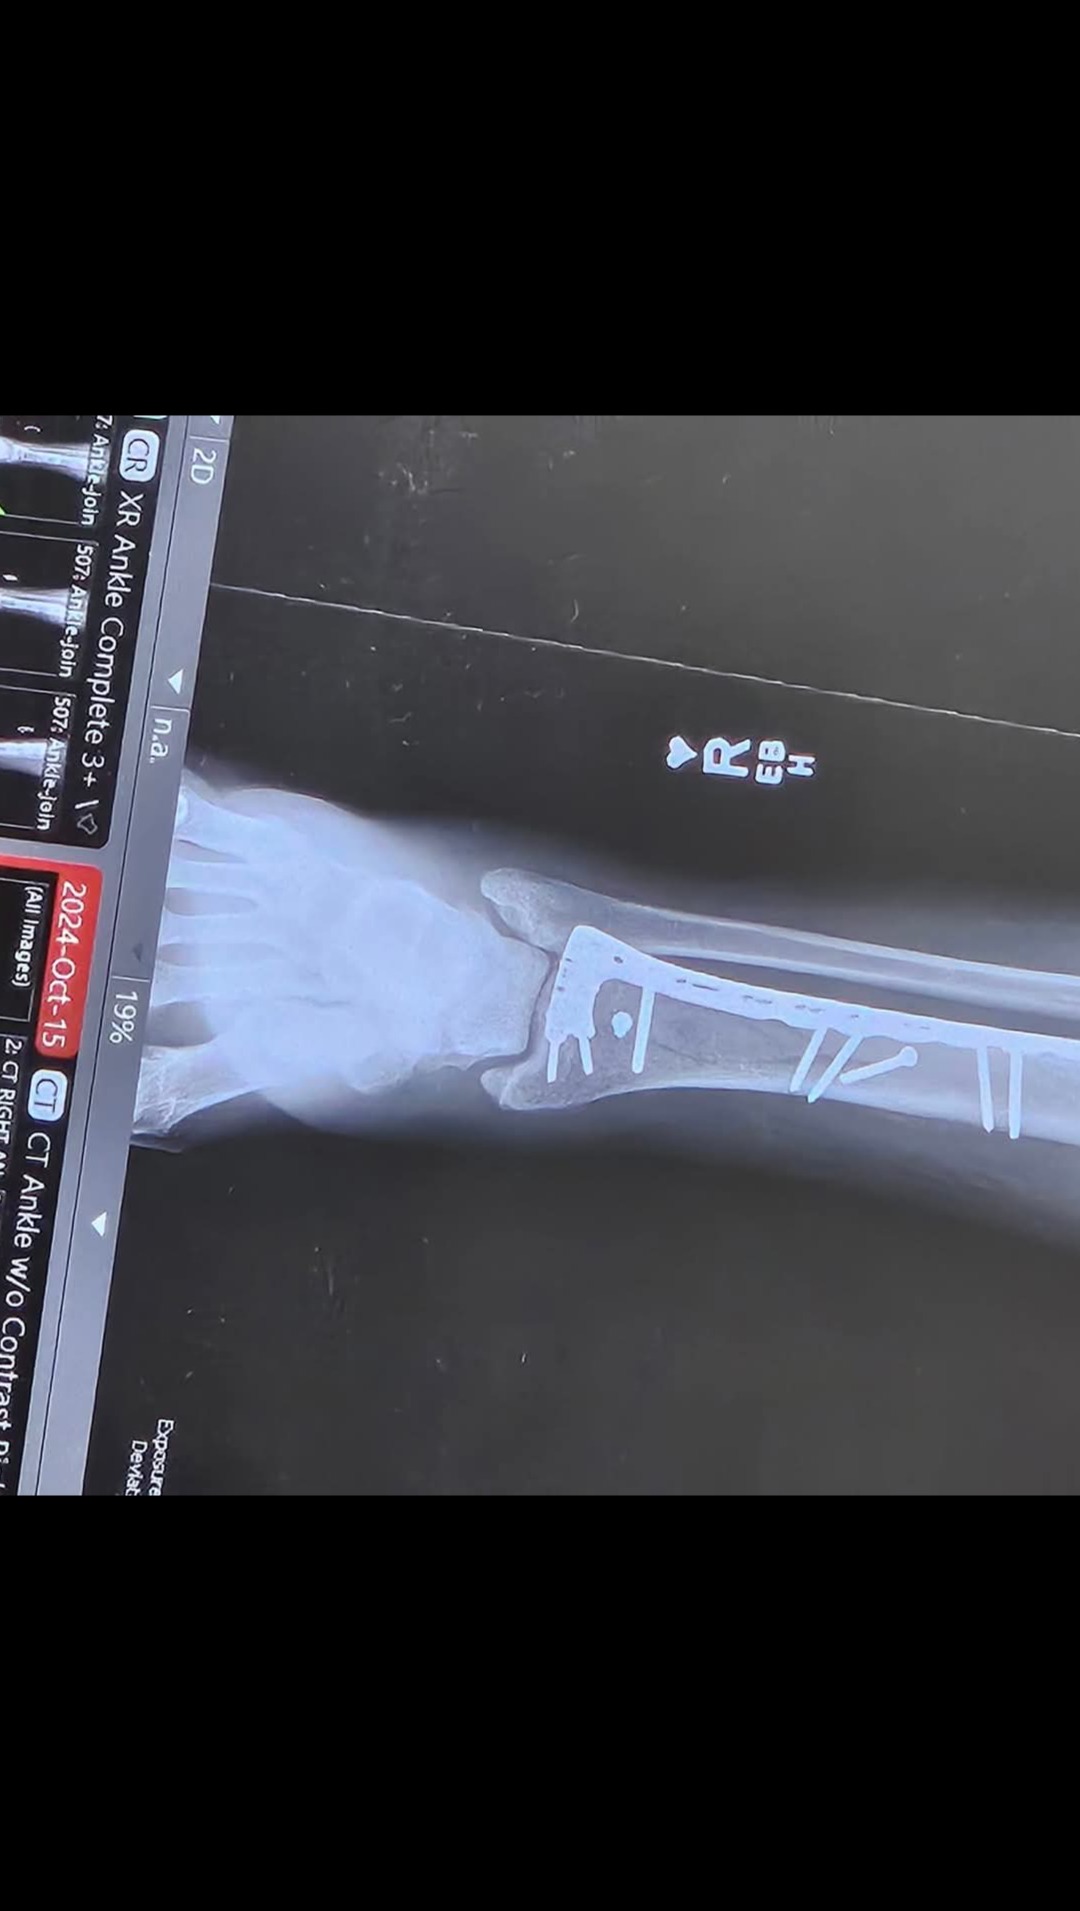

So I know this may be a long shot, but a couple of months ago, my friend's husband had a horrible accident falling through some stairs over 8 feet breaking his tibia and fibia shattering his ankle.